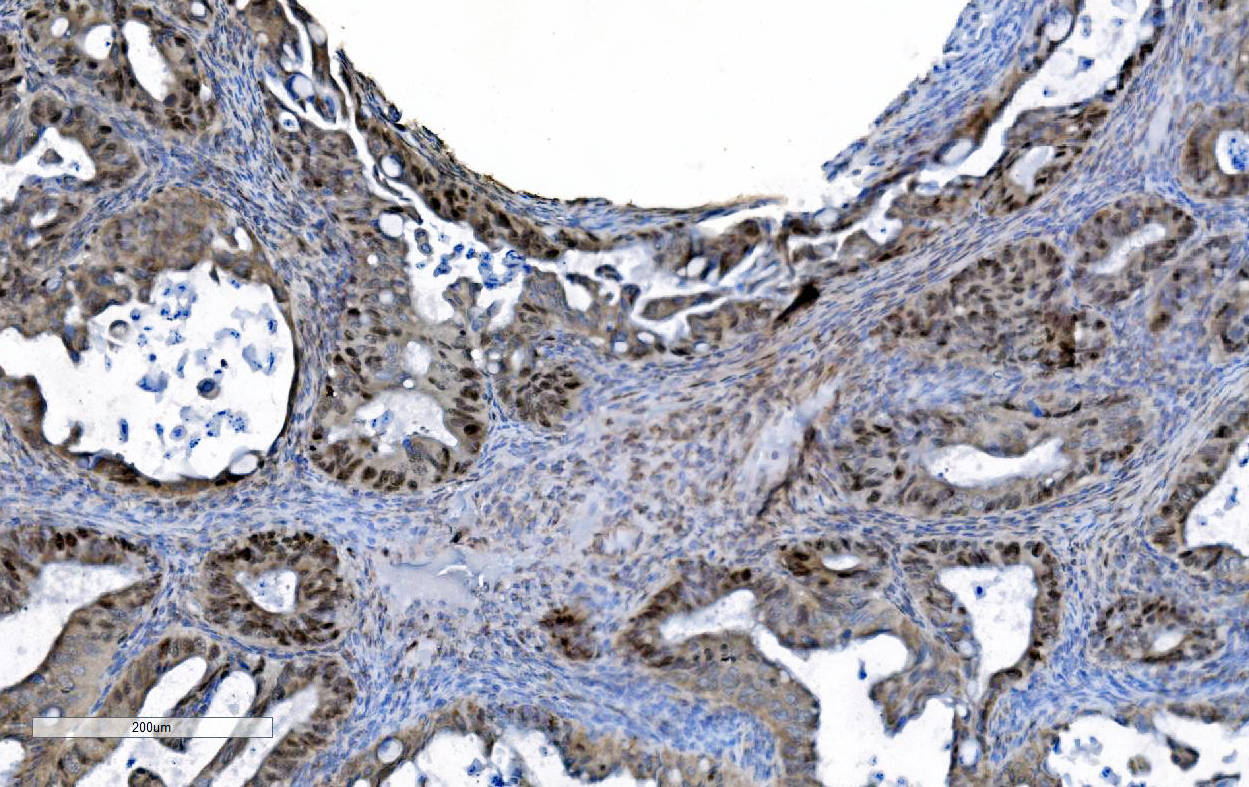

IHC analysis of MCM6 using anti-MCM6 antibody (M02755).

MCM6 was detected in a paraffin-embedded section of human breast cancer tissue. Biotinylated goat anti-mouse IgG was used as secondary antibody. The tissue section was incubated with mouse anti-MCM6 Antibody (M02755) at a dilution of 1:200 and developed using Strepavidin-Biotin-Complex (SABC) (Catalog # SA1021) with DAB (Catalog # AR1027) as the chromogen.